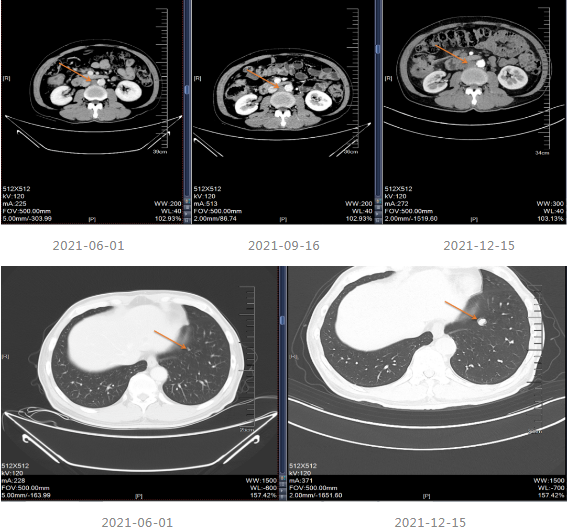

2021.06-01复查影像学提示肝胃间隙及腹膜后淋巴结较前增大,疗效评价PD。

2021-06-08至2021-12-11采用“贝伐珠单抗+Cap”治疗8个周期。

2021-12-15影像学复查提示疾病进展。

▌三线治疗

2021-12-20至2022-03-21更改化疗方案,采用“贝伐单抗+FOLFOX6方案”进行治疗。